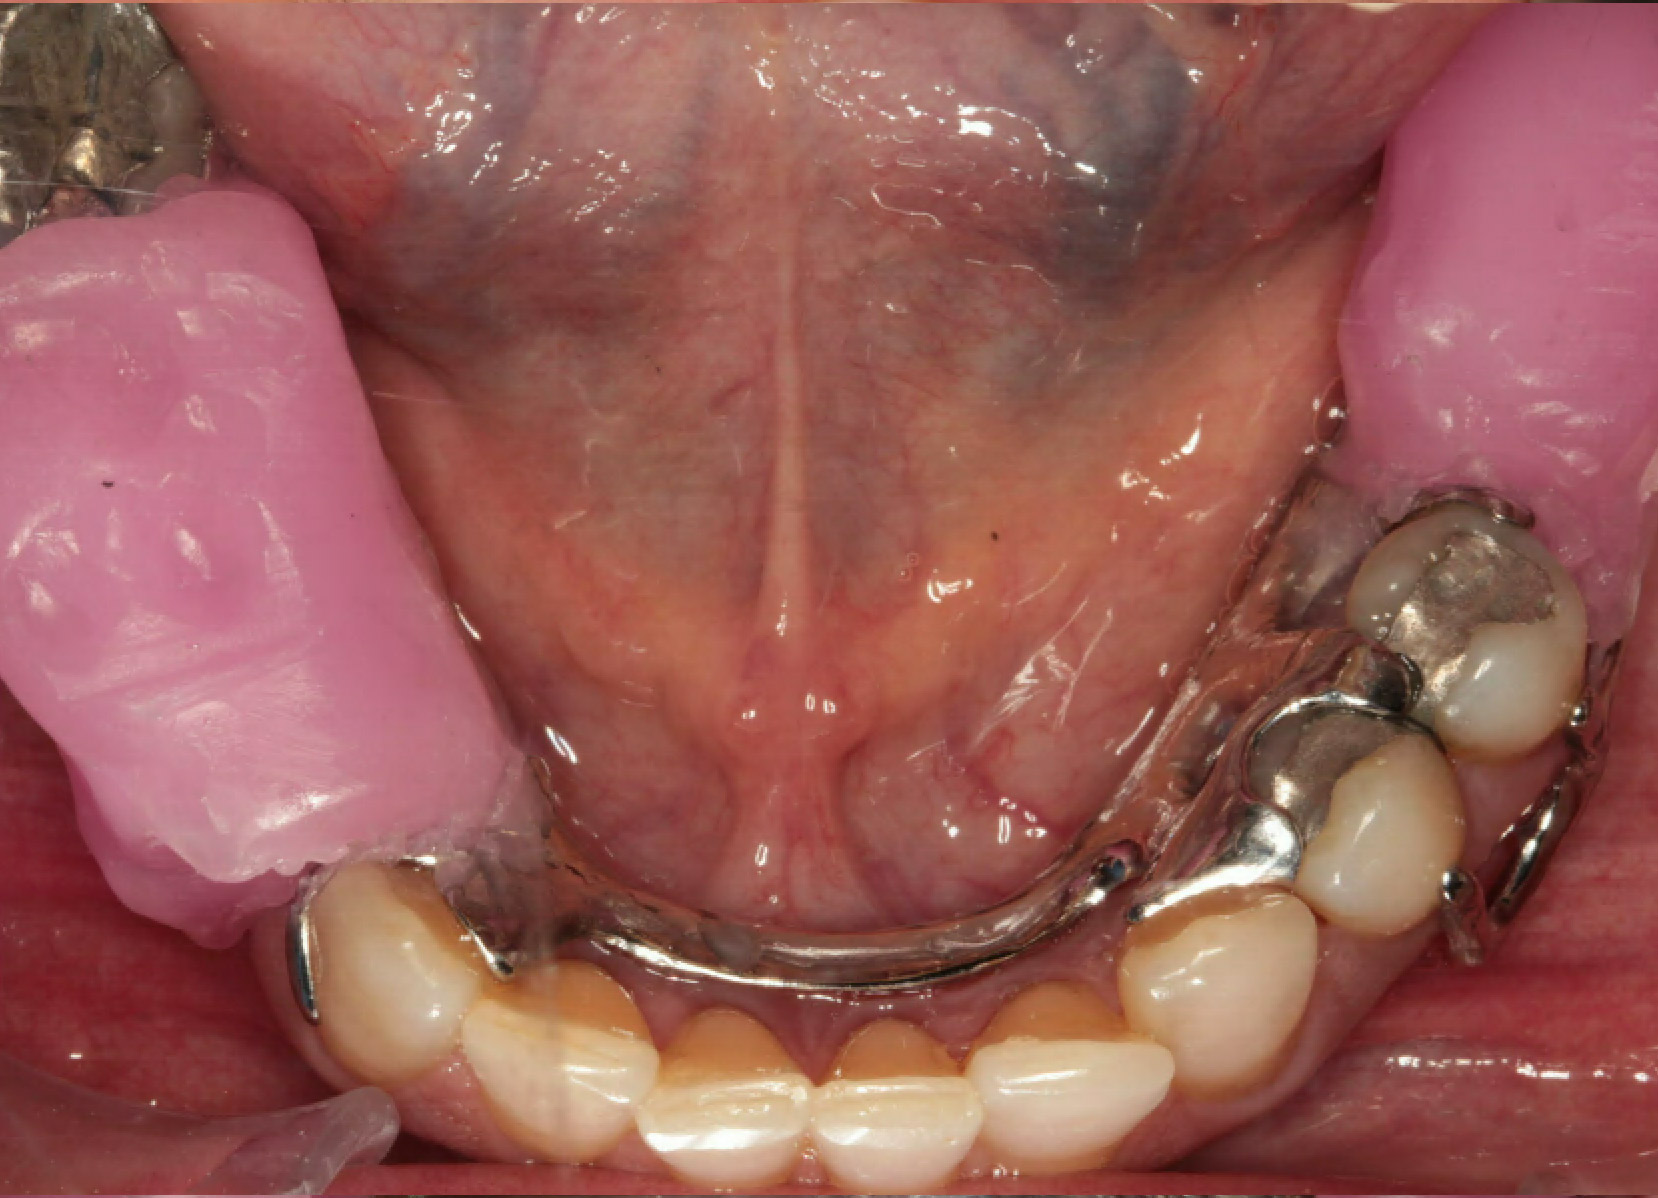

Intra Oral Pictures (3)

(Treatment in progress)

Intra Oral Pictures (4)